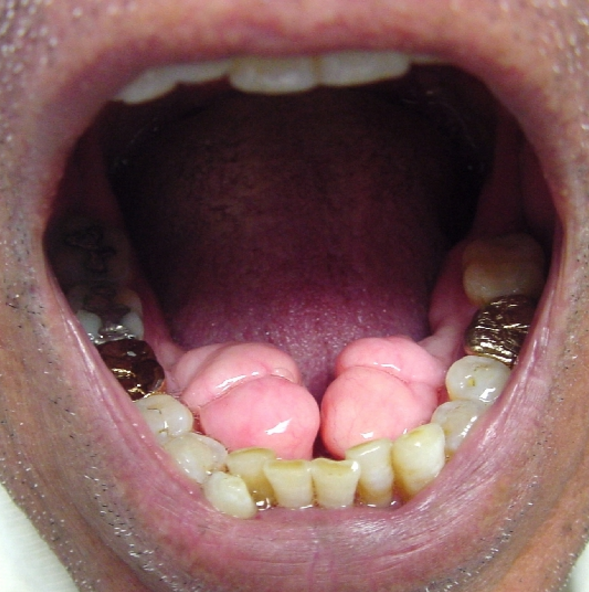

🔺Clinical features

1. Painless, beadlike enlargement of the interdental papilla and extends to facial and lingual gingival margins

2. Maxillary & mandibular anterior regions

3. When uncomplicated by inflammation is mulberry shaped, firm,pale pink, and resilient , with a minutely lobulated surface and no tendency to bleed

4. Project from beneath the gingival margin